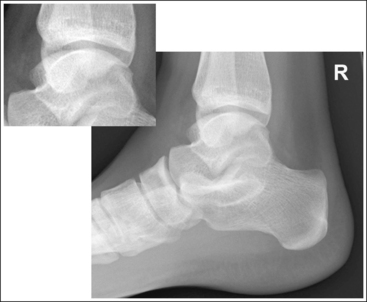

The ankle is in a lateral projection. The domes of the talus are superimposed, the tibiotalar joint is open, and the distal fibula is superimposed by the posterior half of the distal tibia.

• Effect of lower leg positioning on talar dome superimposition. Often, if the knee is not fully extended (Figure 6-59) or if the distal tibia is not elevated to place the lower leg parallel with the IR in a patient with large upper thighs, the proximal tibia is positioned farther from the imaging table than the distal tibia. The resulting image demonstrates the lateral talar dome proximal to the medial talar dome and the height of the longitudinal arch appears less than it actually is because the cuboid shifts anteriorly and the navicular bone moves posteriorly in this position and the talocalcaneal joint will be narrowed (see Image 43). If the distal tibia is positioned farther from the table than the proximal tibia, the medial talar dome is demonstrated proximal to the lateral dome, and the height of the longitudinal arch appears greater than it actually is because the cuboid shifts posteriorly and the navicular bone moves anteriorly in this position and the talocalcaneal joint will be widened (see Image 44). When viewing a lateral ankle projection that demonstrates one of the talar domes proximal to the other, evaluate the height of the longitudinal arch and the degree of talocalcaneal joint visualization to determine which dome is the proximal dome. If the navicular bone is superimposed over more of the cuboid than expected and a narrowed talocalcaneal joint is seen, the lateral dome is the proximal dome. If the navicular bone is superimposed over less of the cuboid than expected and a wider talocalcaneal joint is seen, the medial dome is the proximal dome.

• Effect of foot positioning on talar dome superimposition. To demonstrate accurate AP alignment of the talar domes, position the lateral surface of the foot parallel with the IR. If this surface is not parallel with the IR, the talar domes are demonstrated one anterior to the other. When the leg is rotated more than needed to place the lateral foot surface parallel with the IR (leg externally rotated), as shown in Figure 6-60, the medial talar dome is demonstrated anterior to the lateral talar dome (see Image 45). If the leg is not rotated enough to place the lateral foot surface parallel with the IR (leg internally rotated), as shown in Figure 6-61, the medial talar dome is demonstrated posterior to the lateral talar dome (see Image 46). When taking a lateral ankle projection that demonstrates one of the talar domes anterior to the other, observe the position of the fibula in relation to the tibia to determine how the patient should be repositioned. On most lateral ankle projections with accurate positioning, the fibula is positioned in the posterior half of the tibia. On a lateral projection with poor positioning, if the fibula is demonstrated more posteriorly, the medial dome is anterior and the patient was positioned with the forefoot depressed and the heel elevated (leg externally rotated), as shown in Figure 6-60. If the fibula is demonstrated more anteriorly, the medial domes are posterior and the patient was positioned with the forefoot elevated and the heel depressed (leg internally rotated), as shown in Figure 6-61.

The long axis of the foot is positioned at a 90-degree angle with the lower leg.

• In most cases, when the patient is relaxed, the foot rests in plantar flexion. Plantar flexion results in a forced flattening of the anterior pretalar fat pad, reducing its usefulness in the detection of joint effusion (see Image 47). Consequently, it is best to dorsiflex the patient's foot, placing its long axis at a 90-degree angle with the lower leg. This positioning also places the tibiotalar joint in a neutral position and helps prevent the leg from rolling too far anteriorly. Anterior foot rotation elevates the heel and rotates the foot.